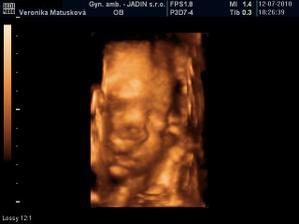

Adamko - 3D/4D

No tot vidno, že je náš syn, sa hanbil a hanbil až sa ukazovať nechcel....ale niekedy sa to podarilo, aj ked to nie je nejaká sláva. Pán doktor nám potvrdil chlapčeka, tak sme radi, vajká ukazoval ako len vedel len toho pipíka stále schovával. Ale je to za nami, pán doktor nás pekne popísal čo je kde, poodmeral nás a povedal, že je všetko v poriadku.